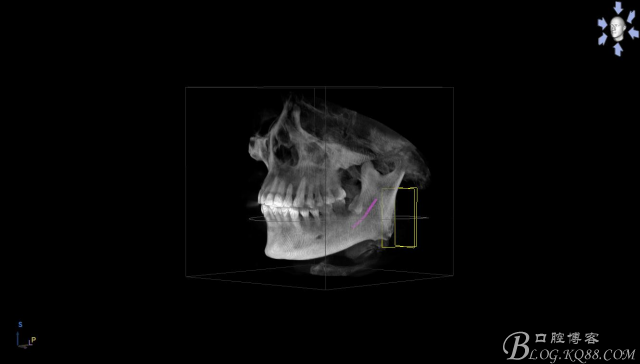

一、術(shù)前CBCT影像資料